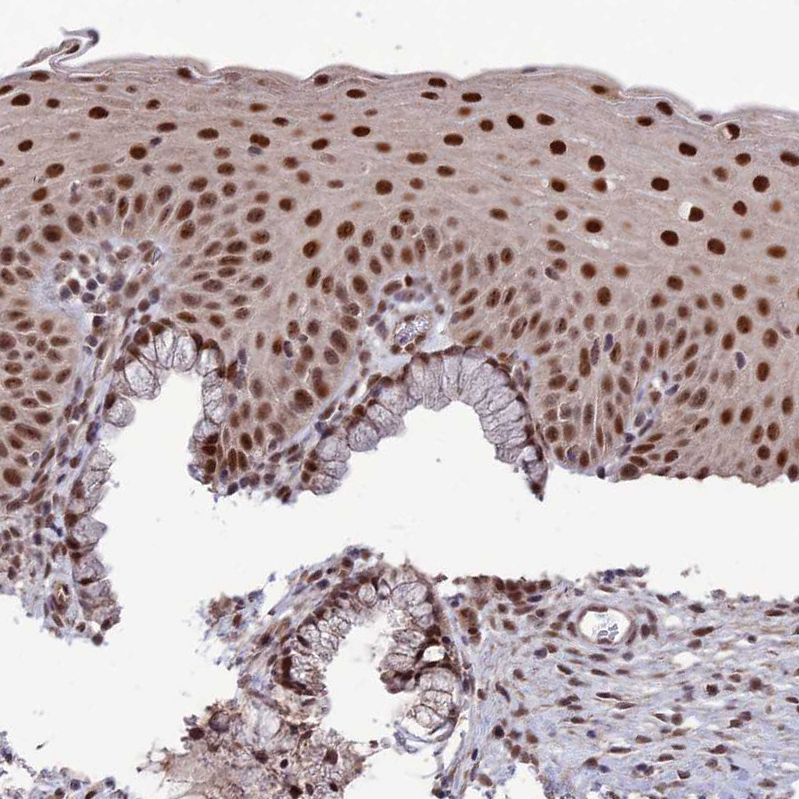

Immunohistochemical staining of human testis shows strong nuclear positivity in cells in seminiferous ducts.